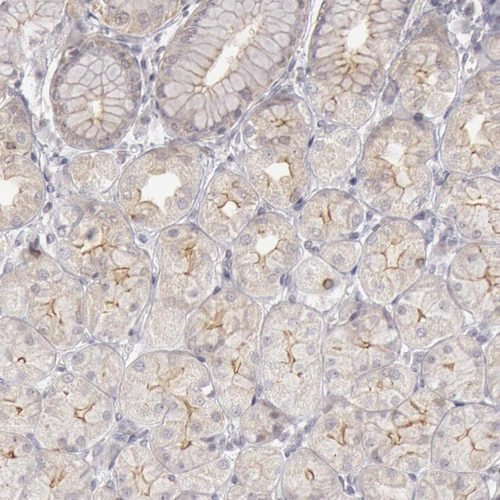

Immunohistochemical staining of human stomach shows moderate membranous positivity in glandular cells.